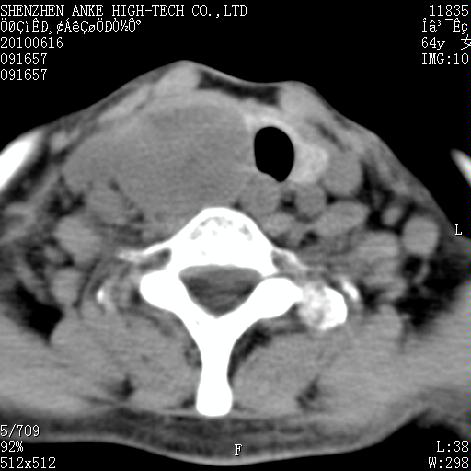

标题: CT27132:患者女,64岁,颈部及全身多处包块,现觉吞咽困难4 [打印本页]

标题: CT27132:患者女,64岁,颈部及全身多处包块,现觉吞咽困难4

右侧甲状腺占位,肿瘤可能性大,癌

右侧甲状腺癌伴右颌下腺淋巴结转移

右侧甲状腺癌伴淋巴结转移

右侧甲状腺癌伴淋巴结转移可能性大

右侧甲状腺癌伴淋巴结转移可能性大。

右侧甲状腺癌伴右颌下腺淋巴结转移!建议增强!